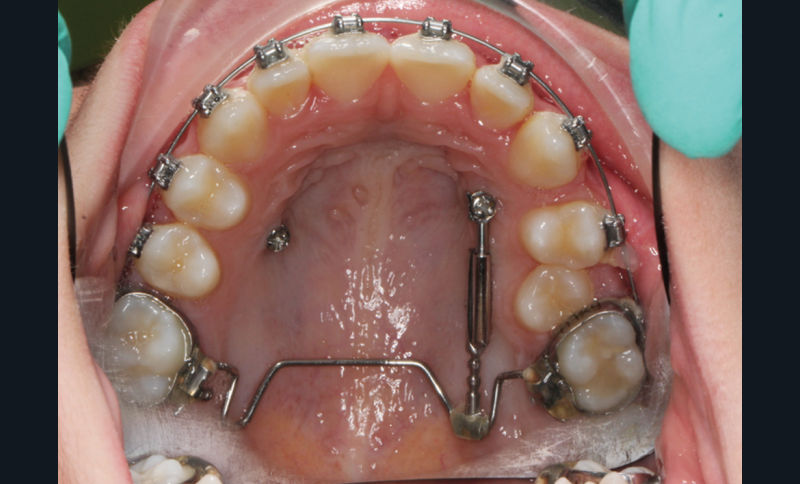

À côté de la coopération moindre qu’ils exigent, les ancrages squelettiques présentent également l’avantage de répondre à des indications très variées : correction des sourires gingivaux (Dr Skander Ellouze, fig. 3a-c), distalisation ou mésialisation molaire, supports pour les masques faciaux, mini transpalatin sur vis après expansion, ressorts de rétraction pour mettre en place les canines incluses sans léser les racines des dents adjacentes [3] (Dr Stéphane Renger, fig. 4) ou appareils d’expansion maxillaire (Dr Hans Winsauer, Dr Guido Sampersmans, fig. 5a-c)…

Le début et milieu d’après-midi seront consacrés à l’empreinte numérique, désormais utilisée pour les empreintes d’étude, les set-up, le thermoformage. Les Drs Guillaume Lecocq et Stéphane Desplanques monteront le thermoformage et comment ces empreintes numériques peuvent permettre de confectionner des appareils vestibulaires, linguaux, voire des aligneurs (fig. 1 et 2).